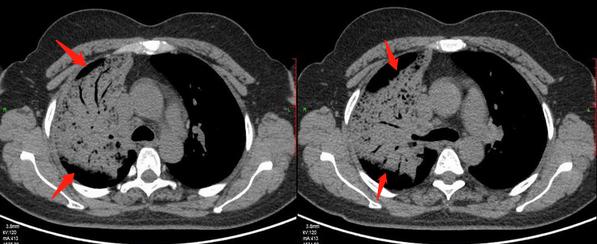

上图这位老人,在72岁的时候发现左侧早期肺癌,觉得年纪大了,没有选择手术也没有采用其他任何治疗。

11年后,老人83岁的时候最后一次来复查,肿瘤已经进展到晚期:

之后就失去联系了。

肺腺癌早期大多进展缓慢,甚至可达数年,仅表现为肺内高危结节(这也是我们呼吁重视胸部体检的原因,通过体检做到早期发现及时处理,解除风险)。